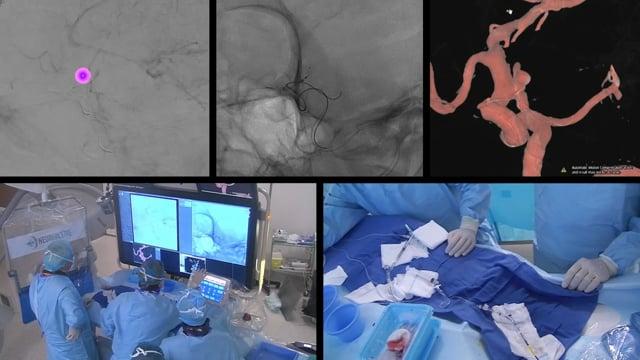

Snare Wars - May the fix be with you

AneurysmsIntrasacular devices

June 4, 2025